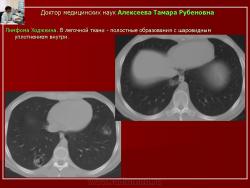

Следует отметить, что не всегда при туберкулезе легких отмечалась классическая скиологическая картина. Трудности в постановке диагноза туберкулеза возникали при появлении множественных полостных образований в легких с тонкими стенками на фоне неизмененной легочной ткани. В отдельных полостях определялись шаровидные массы, что заставило расценить выявленные в легких изменения как проявления аспергиллеза (рис. 7).

Рис. 7. Б-ного Р. Лимфома Ходжкина. В легочной ткани - полостные образования с шаровидным уплотнением внутри.

Однако при микроскопическом исследовании мокроты больного Р., страдающего лимфомой Ходжкина, были обнаружены микобактерии туберкулеза. На фоне противотуберкулезной терапии отмечена положительная динамика, а в дальнейшем и полная регрессия изменений в легких.